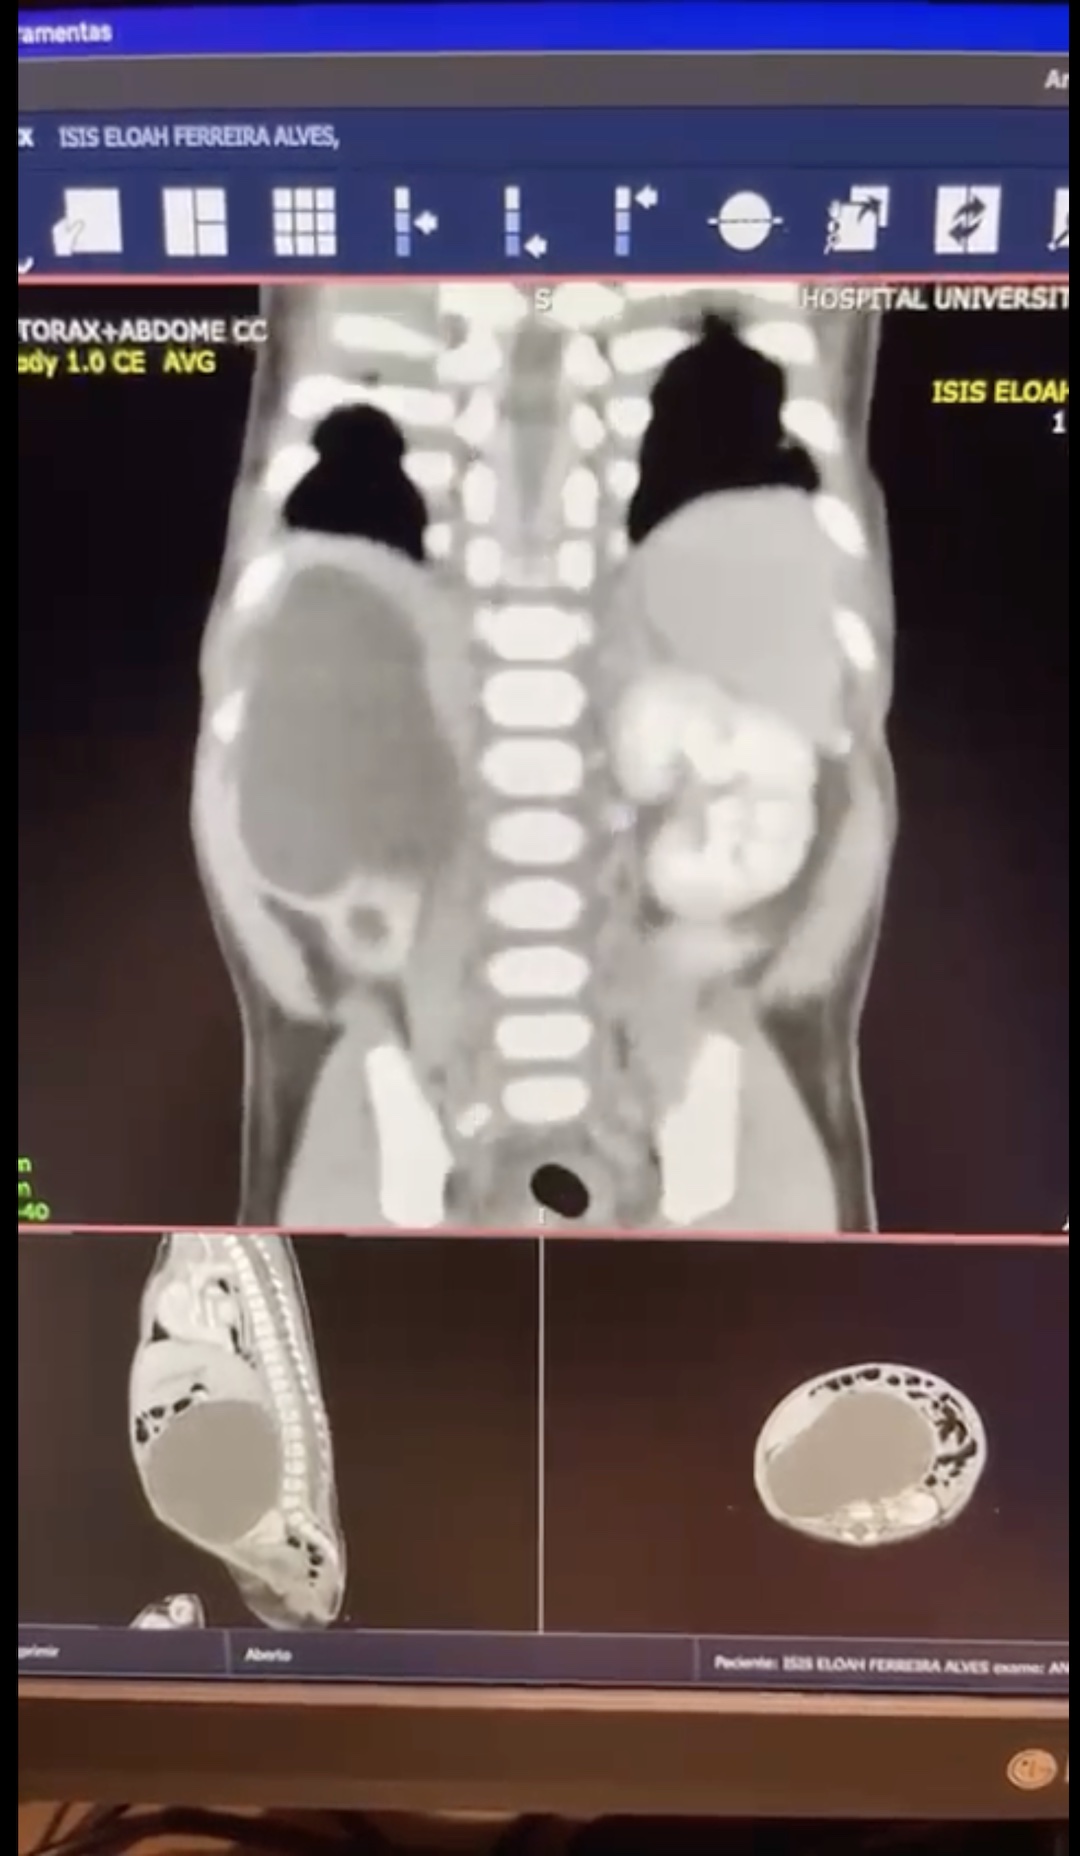

“Mais ou menos 10% de todas as crianças que nascem no mundo inteiro vão ter alguma malformação congênita e podem acontecer em todos os órgãos do corpo humano. No caso de Isis, o quadro estava relacionado à estrutura que dá origem aos rins. A menina nasceu com quatro rins ao todo, dois em cada lado do corpo, sendo que os rins inferiores estavam ligados. A condição é chamada de “rins em ferradura”, por causa do formato adotado pelos órgãos unidos, mas não oferece riscos a Isis.

O fato de uma criança nascer com mais de dois rins, por si só, não é um problema – porém, um dos rins de Isis estava obstruído, causando um inchaço que prejudicava os órgãos vizinhos. “Esse rim estava tão grande que impedia os outros órgãos de funcionar a contento. O intestino dela, o diafragma, os pulmões, estavam completamente comprimidos por essa grande massa”, conta Buson.